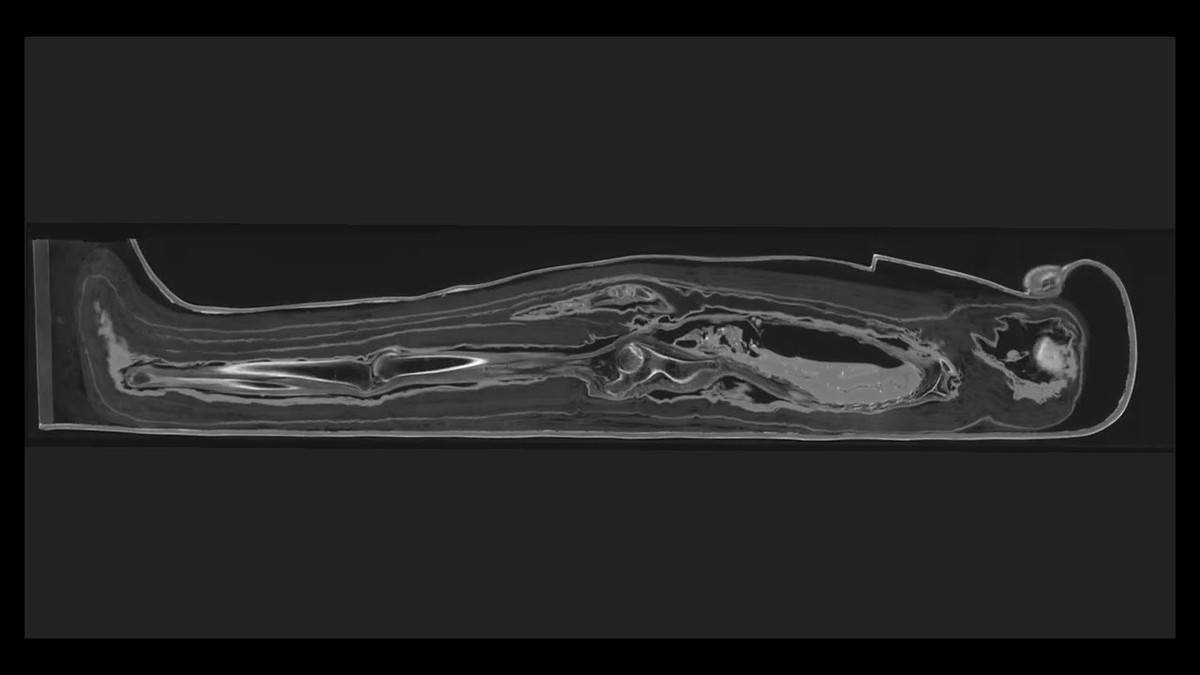

Bảo tàng Field ở Chicago, Mỹ là nơi lưu giữ, bảo quản hơn chục xác ướp Ai Cập cổ đại. Trong số này có một xác ướp "đặc biệt" khiến các nhà nghiên cứu bối rối suốt nhiều năm. Xác ướp nữ quý tộc Ai Cập có tên Chenet-aa là một trong số đó. Theo kết quả nghiên cứu mới công bố, các chuyên gia đã dùng máy chụp cắt lớp vi tính (CT) để kiểm tra xác ướp quý bà Chenet-aa có niên đại khoảng 3.000 tuổi.

Thông qua chụp cắt lớp vi tính (CT) tạo ra hình ảnh 3D của vật thể bằng cách xếp chồng hàng nghìn bản scan X - quang lên nhau dựa trên kỹ thuật số, giới nghiên cứu đã giải mã được bí mật này. Theo họ, người Ai Cập thời cổ đại đã tạo vết rạch ở phía sau hộp cartonnage và làm mềm vật liệu bằng hơi ẩm để nó trở nên dẻo dai.

Ảnh chụp CT cũng hé lộ nhiều chi tiết mới về sức khỏe của quý bà Chenet-aa trong những ngày cuối đời. Nữ quý tộc qua đời ở cuối tuổi 30 hoặc đầu tuổi 40 nhưng chưa thể xác định nguyên nhân tử vong của bà.

Giới chuyên gia cũng phát hiện xác ướp của quý bà Chenet-aa có đặt đôi mắt nhân tạo ở hốc mắt để giúp bà có thể nhìn được ở thế giới bên kia. Ảnh: The Field Museum.